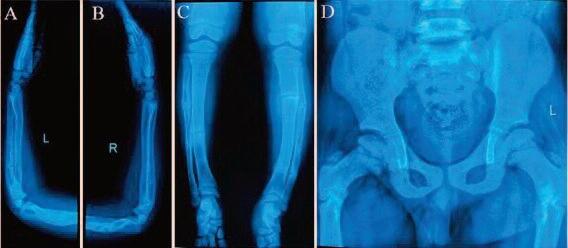

Osteogenesis Imper fecta, Penyakit

Langka Zehan Almira 11 12 15 16 18 20 26 32

Namun, di balik kepandaiannya, Zehan mengidap Osteogenesis Imperfecta (OI) Itu merupakan penyakit langka yang memengaruhi pertumbuhan tulangnya Sehingga membuatnya tumbuh lebih lambat dibandingkan anak-anak seusianya.

Apa sebenarnya OI? Penyakit osteogenesis imperfecta yang diderita Zehan adalah kelainan genetik Penyakit ini timbul karena disebabkan oleh mutasi genetik yang mengakibatkan produksi kolagen dalam tulangnya berkurang, sehingga tulang menjadi rapuh dan mudah patah

Osteogenesis Imperfecta yang dikenal juga dengan Brittle Bone Disease adalah gangguan pada struktur tulang sehingga membuat tulang tidak kokoh

Kolagen adalah protein yang sangat penting dalam struktur dan kekuatan tulang Dengan adanya mutasi genetik, produksi kolagen dalam tubuh Zehan berkurang, sehingga tulangnya menjadi rapuh dan mudah patah

Gejala osteogenesis imperfecta biasanya sudah muncul sejak lahir, meskipun baru terdeteksi pada saat anak mulai bersekolah atau bahkan lebih tua Pada umumnya, gejala osteogenesis imperfecta juga dapat bervariasi, seperti mudah mengalami patah tulang, warna sklera mata yang kebiruan, dan pertumbuhan yang lambat

Hingga saat ini, belum ada pengobatan yang dapat menyembuhkan osteogenesis imperfecta secara total Namun ada beberapa pengobatan dan strategi yang dapat digunakan hanya bertujuan untuk memperkuat struktur tulang dan mengurangi risiko patah tulang dengan beberapa cara pengobatan yang umum digunakan seperti terapi hormon, konsumsi makanan vitamin D dan kalsium, erjemur di pagi hari, dan pemeriksaan rutin oleh dokter

Berdasar informasi yang dihimpun dari berbagai sumber, diperkirakan hanya ada sekitar 300 ribu kasus osteogenesis impefecta di seluruh dunia OI umumnya telah dialami penderitanya sejak lahir. Meski demikian, penyakit tulang yang langka ini sering kali baru terdeteksi di usia kanak-kanak atau bahkan setelah dewasa.@. g st

Setiap pengidap osteogenesis imperfecta mengalami kondisi yang berbeda-beda tergantung tipe OI yang diderita. Yuk, kenali tipe-tipe osteogenesis imperfecta yang dilansir Media Sehat dari berbagai sumber.

Ini adalah jenis osteogenesis imperfecta yang paling ringan dan paling banyak ditemukan Dalam kasus OI tipe I, tubuh menghasilkan kolagen yang berkualitas tapi dalam jumlah yang rendah. Akibatnya, tulang menjadi rapuh Anak-anak dengan OI tipe I biasanya mengalami patah tulang akibat trauma ringan Sedangkan pada orang dewasa, patah tulang tidak sering terjadi Penyakit ini juga bisa memengaruhi gigi dan menyebabkan gigi mudah retak dan bolong

Ini adalah bentuk OI yang paling parah dan bisa mengancam jiwa Dalam kasus OI tipe II, tubuh tidak menghasilkan cukup kolagen atau menghasilkan kolagen yang berkualitas buruk OI tipe II

bisa menyebabkan kelainan bentuk tulang. Anakanak yang terlahir dengan jenis osteogenesis imperfecta ini mungkin akan memiliki dada yang menyempit, tulang rusuk yang rusak, atau paru-paru yang tidak berkembang dengan sempurna Bayi yang terkena OI tipe II bisa gugur dalam rahim atau meninggal tidak lama setelah lahir

Jenis osteogenesis imperfecta ini juga cukup parah dan menyebabkan tulang mudah patah Dalam kasus OI tipe III, tubuh menghasilkan cukup kolagen, tapi kualitasnya buruk OI tipe III bisa menyebabkan tulang bayi mulai patah, bahkan sebelum lahir Anak dengan jenis OI ini juga akan mengalami kelainan bentuk tulang yang mungkin memburuk saat ia bertambah besar

Osteogenesis imperfecta tipe ini memiliki gejala yang bervariasi mulai dari ringan hingga berat Sama seperti OI tipe III, OI Tipe IV juga disebabkan karena tubuh menghasilkan kolagen yang berkualitas buruk Anak dengan jenis OI ini biasanya dilahirkan dengan kaki tertekuk, meskipun kondisi ini bisa membaik seiring bertambahnya usia. g en